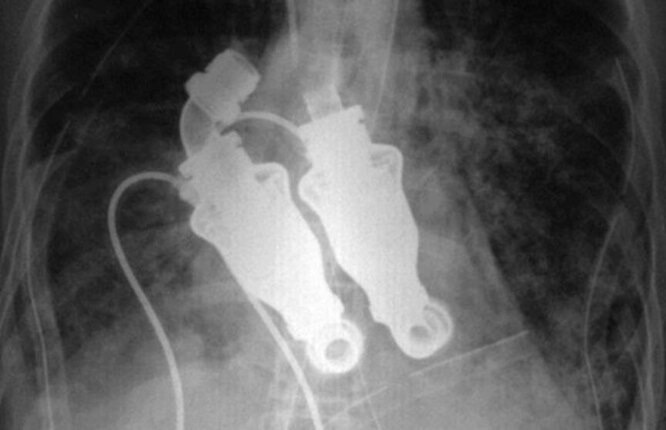

У него не было пульса — но он был жив: реальный случай из медицины

Представьте: врачи останавливают сердце человека… и вынимают его из груди. А пациент при этом остаётся живым. Звучит как сюжет научной фантастики. Но это реальная медицинская история, которая произошла в США и навсегда изменила представление о возможностях современной медицины. Иногда жизнь держится на ниточке. Иногда — на машине. В начале 2011 года 55-летний американец по имени Крейг Льюис оказался на грани смерти. Его сердце разрушала редкая и агрессивная инфекция — амилоидоз. Болезнь буквально превращала сердечную ткань в хрупкий, бесполезный материал. Обычные лекарства не помогали. Пересадка сердца была слишком рискованной. Врачи понимали: времени почти не осталось. И тогда они решились на эксперимент, который раньше казался невозможным. Хирурги удалили сердце пациента полностью. На его место установили специальное устройство — систему SynCardia Total Artificial Heart. Это полностью искусственное сердце, которое работает благодаря внешнему компрессору и системе трубок. Но в истории